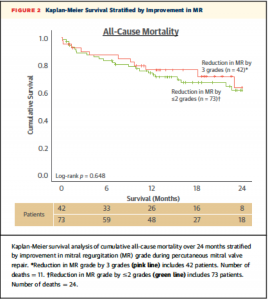

術後のMR重症度改善の程度(MR gradeがどれだけ下がったか)により分類した2群によるK-M curveでは、24ヶ月の死亡率について有意な差を認めなかった(Figure 2)。

(Figure 2)

(Figure 2)